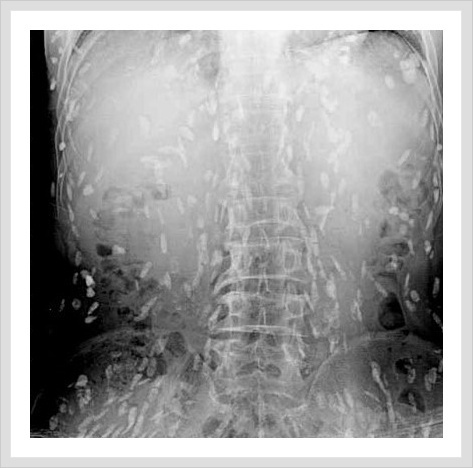

(혐오주의) 생선회 먹고 기생충이 온몸에 퍼진 남성

그냥 엑스레이사진인데 기생충이 많아요! 전 그닥 징그럽지는 않았는데 좀 소름돋긴했어요